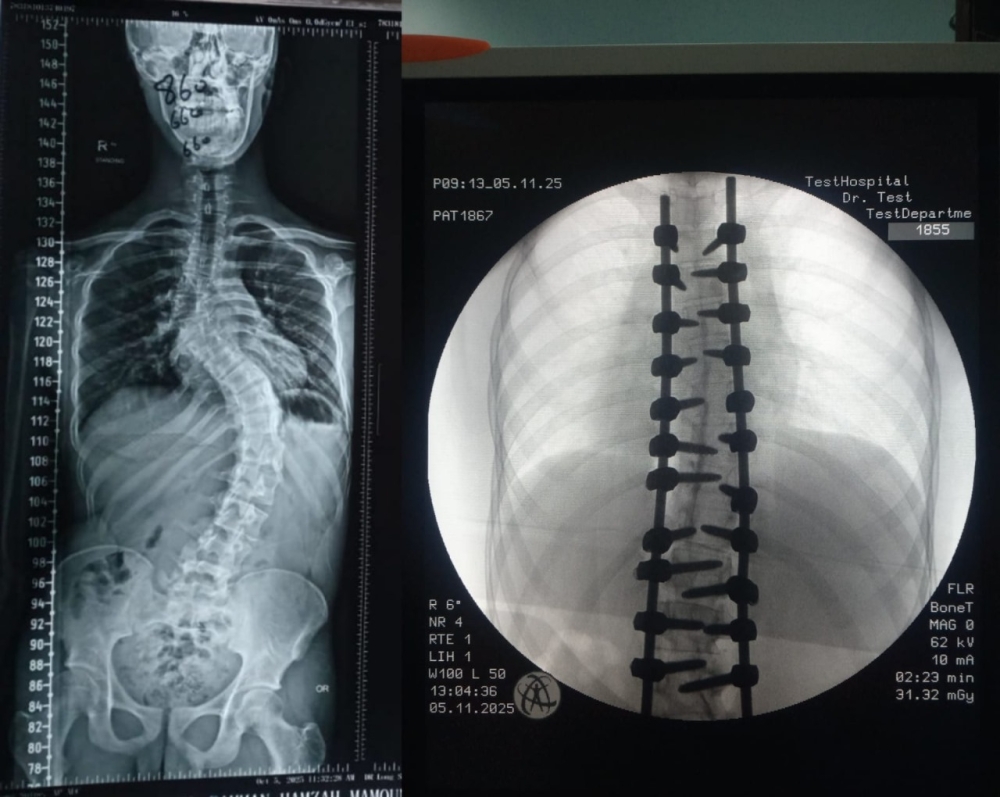

شهد قسم جراحة العمود الفقري في مستشفانا إنجازا طبيا مميزا تمثّل في إجراء تدخل جراحي معقّد لتصحيح جنف العمود الفقري لدى أحد المرضى الذين يعانون من تشوّه حاد في الفقرات.

وقد أُجريت العملية باستخدام جهاز الملاحة الجراحية المتقدّم، الذي أتاح دقةً عالية في التعامل مع التشوّهات البنيوية الشديدة، وسهّل توجيه الأدوات الجراحية ضمن المسار الآمن والمثالي. كما اشتملت العملية على إزالة أجزاء محددة من الأطراف الخلفية للفقرات لتحقيق التصحيح المطلوب واستعادة التوازن والمحاذاة الطبيعية للعمود الفقري.